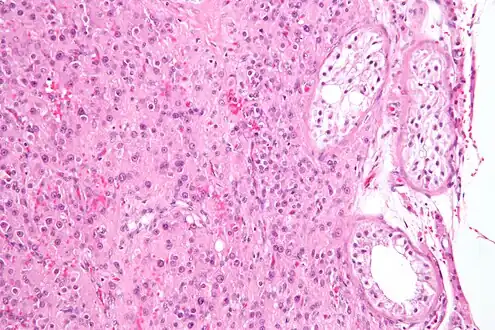

Intermediate magnification micrograph of a Leydig cell tumour, H&E stain

High magnification micrograph of a Leydig cell tumour, H&E stain- Cross-section of seminiferous tubules; arrows indicate location of Leydig cells